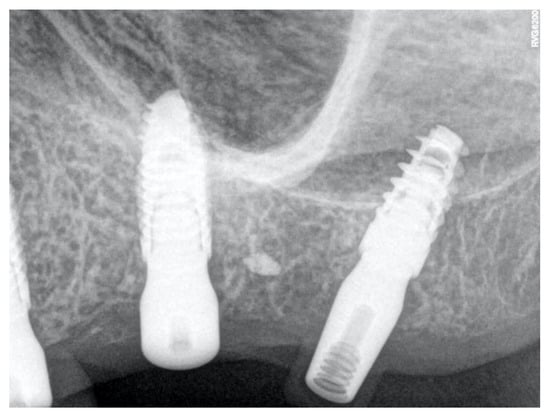

2. Materials and Methods

2.1. Samples

2.2. Laboratory-Based Micro-CT Investigation of the Implant

3.1. Laboratory-Based Micro-CT